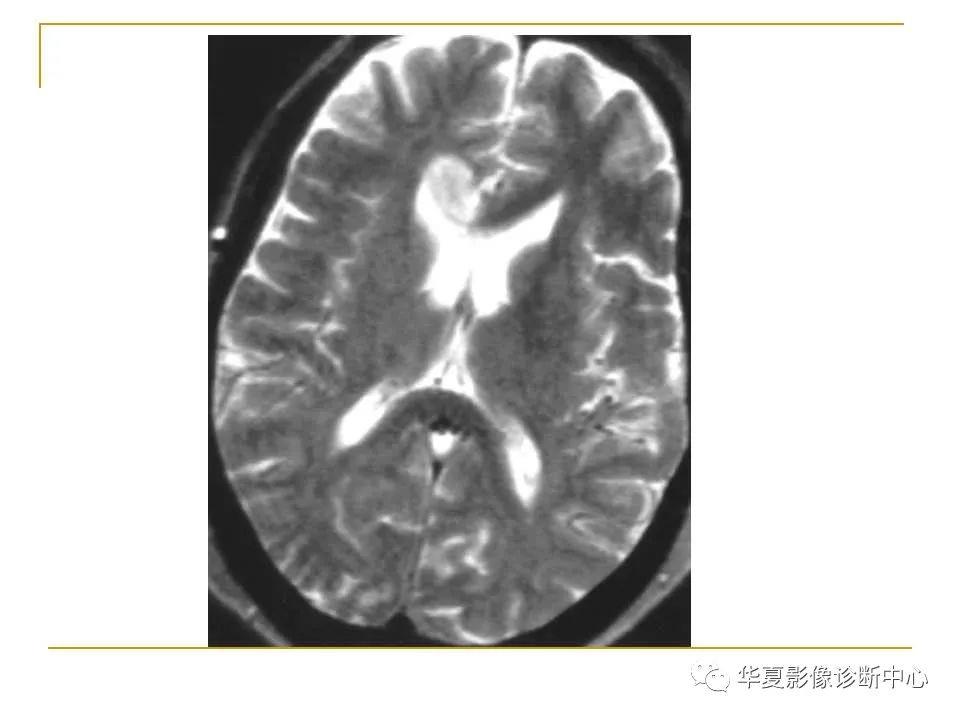

胼胝体解剖及病变大全